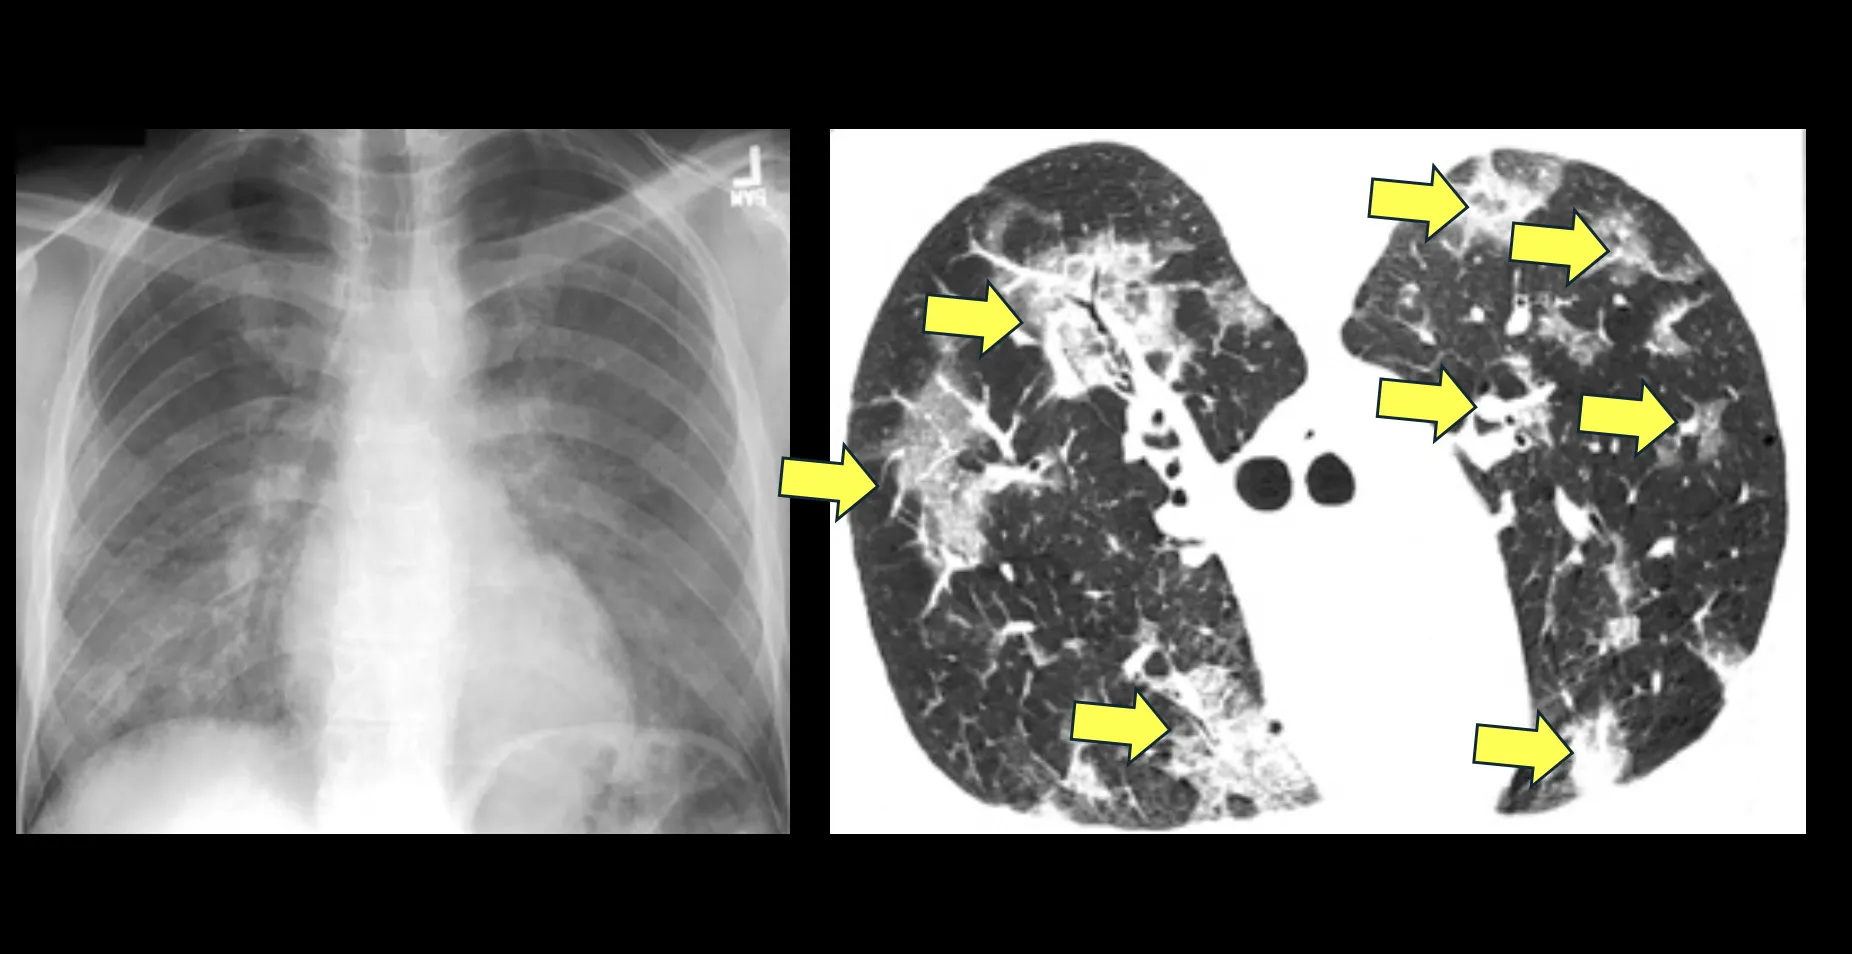

Your question about PjP (Pneumocystis jiroveci pneumonia) makes me think back to the early days of the AIDS epidemic – the mid-1980s through the mid-1990s – when I was a medical intern and infections from this opportunistic organism, then called Pneumocystis carinii or PcP were the leading cause of death among AIDS patients. Many thousands of AIDS patients – probably millions, in fact – died very quickly from overwhelming PcP infections because their immune systems had become severely compromised by the human immunodeficiency virus (HIV). Some chest X-rays and chest CT images from patients with severe Pneumocystis infections are shown in the Figure.

Pneumocystis jiroveci pneumonia.jpg